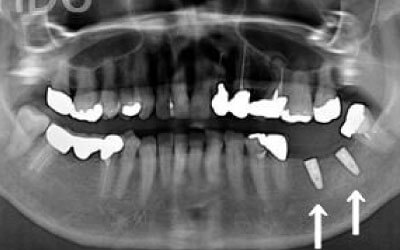

骨が薄い場合は、そのままインプラントすることはお勧めできません。

ただ、事前に骨を増やす治療をしたり、インプラントと同時に骨を増やす治療をしたりすればインプラントをすることは可能です。

1)インプラント治療を行う前に、骨の治療が必要かもしれません。

2)骨の治療から始めると、その分、治療期間が長くなります。

4)骨の状況をしっかり把握するためにも、CT撮影が必須となります。